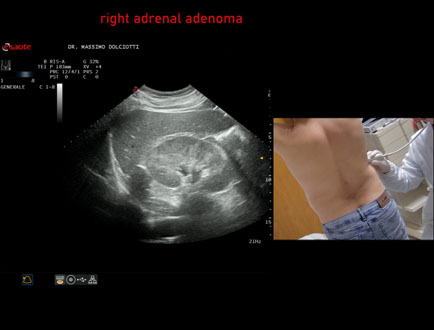

Data inserimento: 18/07/2018

Ecografia del: 13/07/2018

Strumento: Esaote MyLab Twice

Sonda: Convex Multifrequenza 1-8 MHz

Età Paziente: F 73 anni

Motivazione dell'esame: follow up di adenoma surrenalico.

Commento all'esame: le immagini ed il video documentano in sede surrenalica destra, formazione ipoecogena, ovalare, a margini definiti, delle dimensioni di 25x22 mm, da ricondurre ad adenoma surrenalico.

Conclusioni: adenoma del surrene destro (right adrenal adenoma).